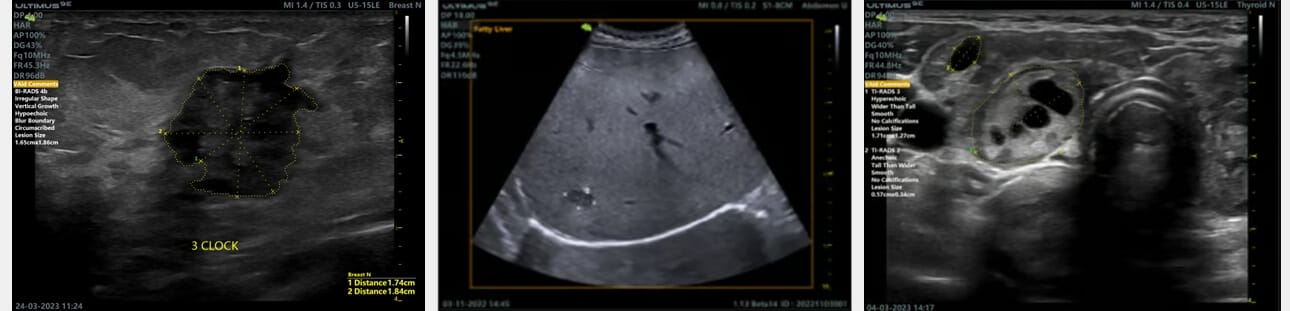

Functia VAID (Vinno Artificial Intelligence Detection) este un modul software de inteligenta artificiala, creat de producatorii ecografelor Vinno, pe o baza foarte mare de date ale unor pacienti cu patologii la nivelul sanului, tiroidei sau ficatului, capabil sa detecteze leziunile, se le evalueze si sa le incadreze intr-un scor standardizat medical.

Functia este disponibila optional pe ecografele Vinno, ajutand specialistii in identificarea leziunilor extrem de mici, care uneori scapa ochiului uman. De asemenea, incadrarea in scorul standardizat (BI-RADS, TI-RADS) ajuta medicul sa stabileasca mai usor urmatorii pasi in investigarea leziunilor si scurteaza timpul de scanare ecografica.

Utilizarea functiei este extrem de simpla, prin activarea acesteia din panoul tactil si inceperea scanarii regiunii anatomice de interes. In timp real, aparatul va identifica leziunile in cadrane colorate in functie de gravitatea patologiei si va afisa scorul BI-RADS/TI-RADS si detalii privind leziunea (forma, masuratori etc). Bucla video se poate salva in arhiva si reveni pe ea, ori de cate ori este nevoie, iar functia VAID va evidentia leziunile.